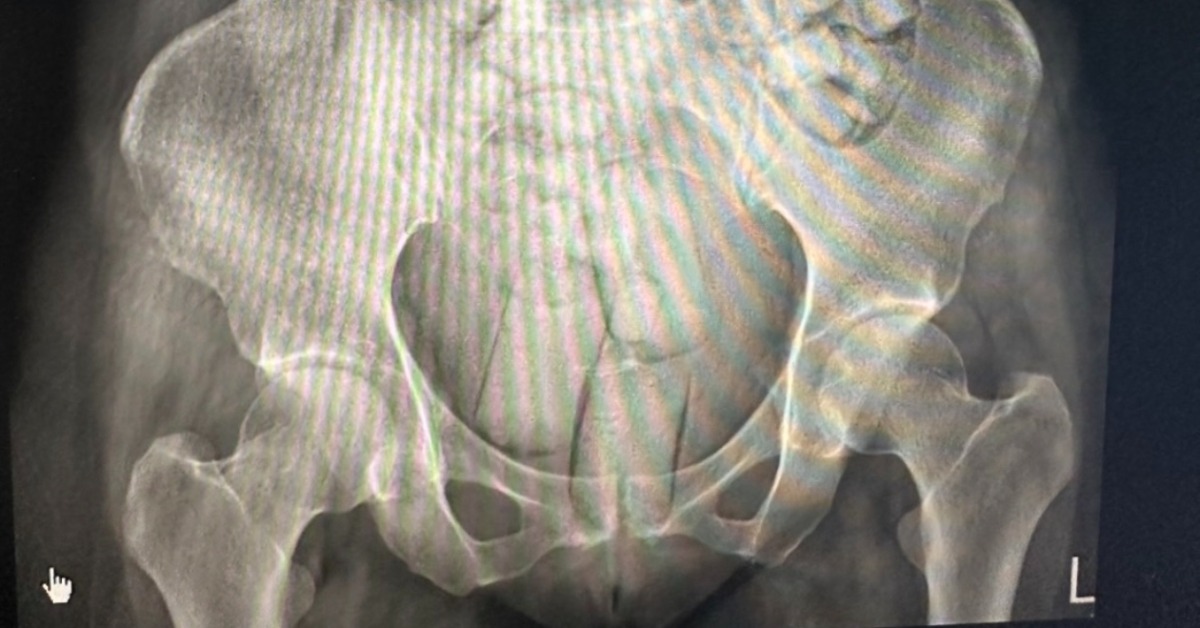

調查指出,台灣與泰國的跨國運毒集團以「免費旅遊」招待外國女子來台,招攬經濟困窘、不熟悉法令的女子以人體夾帶方式運毒。販毒集團將海洛因分裝成可吞食大小的橢圓顆粒,或是可塞入肛門的長條狀,再以防水乳膠膜與保險套包裹,避免毒品在運輸過程中被胃酸腐蝕受損。